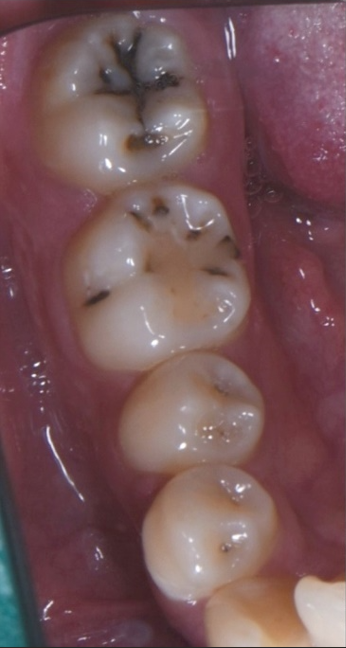

사진을 보시면 아시겠지만, 양쪽 끝 어금니에 검은 충치가 깊게 자리 잡고 있었습니다.

첫째, 치아의 높이가 매우 낮았습니다.

일반적으로 충치 치료 후 크라운을 씌우려면, 충치를 제거한 후에도 일정 높이의 치아가 남아 있어야 합니다.

그러나 이 환자분의 경우, 충치를 긁어내면 치아가 거의 남지 않을 정도였습니다.

잇몸이 드러날 정도로 낮아지면 크라운 치료 자체가 불가능합니다.

둘째, 충치가 신경 가까이까지 깊게 진행되어 있었습니다.

단순히 충치만 제거하면 신경이 노출될 가능성이 높아졌습니다.